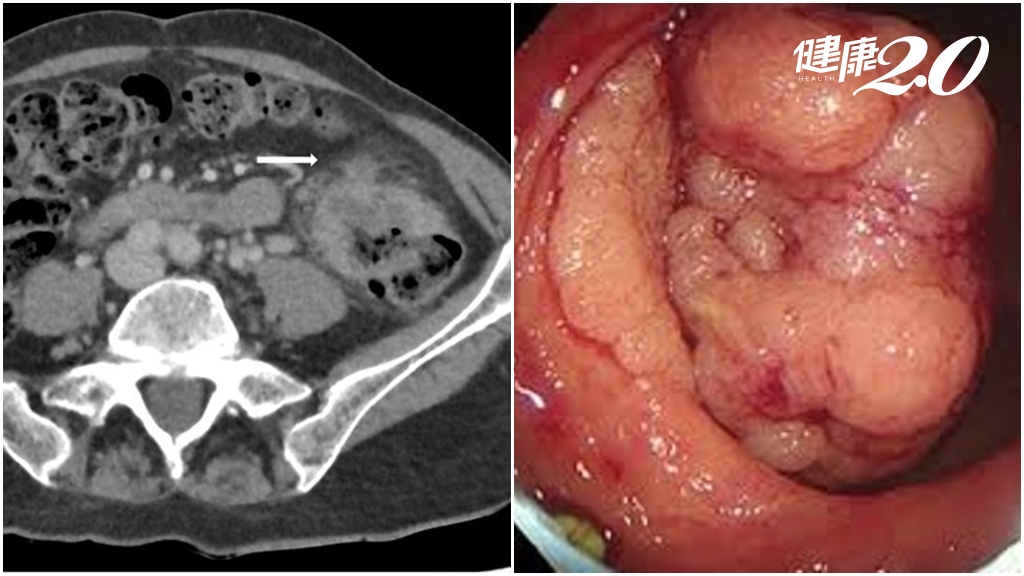

只是頭暈疲累!55歲婦飲食清淡 貧血檢出大腸癌 醫揭多項篩檢可免費